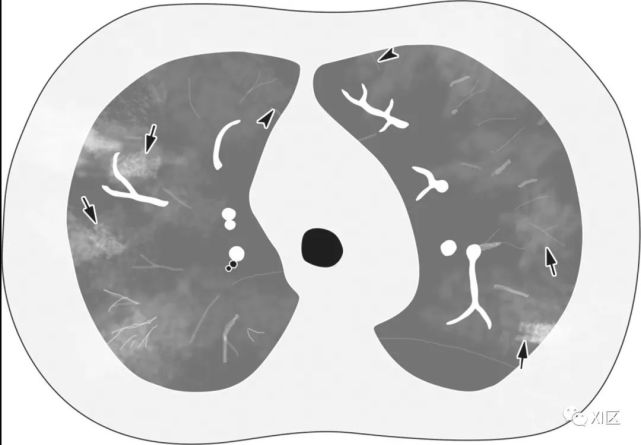

图片

图4 水痘-带状疱疹病毒引起的肺炎显示多灶性1-10毫米清晰或不清楚的结节状阴影(箭),两肺周围有晕或斑片状GGO(箭头)。